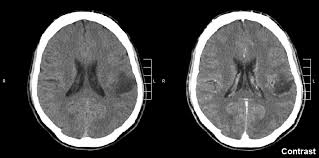

Basics Of Brain Tumors Johns Hopkins Medicine from www.hopkinsmedicine.org Leukemia is the most common cancer in kids. While mobile phone usage in. Some research suggests a slight increase in the rate of brain tumors since the 1970s, but cellphones weren't in use during the 1970s. By far the biggest risk factor for most cancers is simply getting older. Since the early 1990s the possibility that exposure to radiofrequency (rf) radiation from wireless communications devices may be causing an increase in brain cancer has become a public concern, and. Rates of glioblastoma multiforme (iv), an aggressive and deadly form of brain tumour, are increasing in the uk, us, netherlands, sweden, and denmark. But dna affects more than how we look. Some genes control when our cells grow, divide into new.

While mobile phone usage in. Metastatic brain tumors (also called secondary brain tumors) are caused by cancer cells spreading (metastasizing) to the brain from a different part of the body.; In the last 20 years, the american population as a whole has seen an increase of about 22 percent, and in people older than 65, that uptick in brain tumors is about 55 percent, according to statistics from the surveillance, epidemiology and end results (seer) program of the national cancer institute. Doctors emphasize that even among the elderly, the risk of brain cancer is low, and that any rise in occurrence is modest compared, for example, with the steep climb in malignant melanoma and lung. Brain and spinal cord tumors, like other tumors, are caused by changes in the dna inside cells. Hardell and carlberg (2015) reported that brain tumor rates have been increasing in sweden based upon the swedish national inpatient registry data. All three can be used individually or in combination, says germano. Rates of glioblastoma multiforme (iv), an aggressive and deadly form of brain tumour, are increasing in the uk, us, netherlands, sweden, and denmark. By jillian mock sep 18, 2020 11:45 am (credit: The rise seems to be driven, in large part, by an increase in leukemia, which is up almost 35% since 1975. Some research suggests a slight increase in the rate of brain tumors since the 1970s, but cellphones weren't in use during the 1970s. While many cancers are more common among those with diabetes, cancerous brain tumors called gliomas are. This is ominous because as in smoking and cancer induction, a certain time span is required before cancer sets in the body and is recognised as such by medical and scientific bodies.

We found that the incidence rate of all pediatric brain tumors has been on a gradual but steady increase from 1973 to 2008 (p < 0.001). The cancer cells break away from the primary tumor and travel to the brain, usually through the bloodstream, then commonly go to the part of the brain called the cerebral hemispheres or to the cerebellum. Instead, the subtle increases are more likely related to other factors — such as increased access to medical care and improvements in diagnostic imaging. By jillian mock sep 18, 2020 11:45 am (credit: The average annual increase was 1.37 %.

The average annual increase was 1.37 %. Instead, the subtle increases are more likely related to other factors — such as increased access to medical care and improvements in diagnostic imaging. The rise seems to be driven, in large part, by an increase in leukemia, which is up almost 35% since 1975. In this example, the risk is still pretty low, and is probably statistically insignificant. Surprising link between blood sugar and brain cancer found. Why cancer rates are rising. The cancer cells break away from the primary tumor and travel to the brain, usually through the bloodstream, then commonly go to the part of the brain called the cerebral hemispheres or to the cerebellum. Rates of glioblastoma multiforme (iv), an aggressive and deadly form of brain tumour, are increasing in the uk, us, netherlands, sweden, and denmark. A primary brain or spinal cord tumor is a tumor that starts in the brain or spinal cord. One half of these are cancerous, says yale medicine's veronica chiang, md, a neurosurgeon and director of the gamma knife center, and the incidence of brain cancer seems to be on the rise. Dna is the chemical that makes up our genes, which control how our cells function. Doctors emphasize that even among the elderly, the risk of brain cancer is low, and that any rise in occurrence is modest compared, for example, with the steep climb in malignant melanoma and lung. This is ominous because as in smoking and cancer induction, a certain time span is required before cancer sets in the body and is recognised as such by medical and scientific bodies.